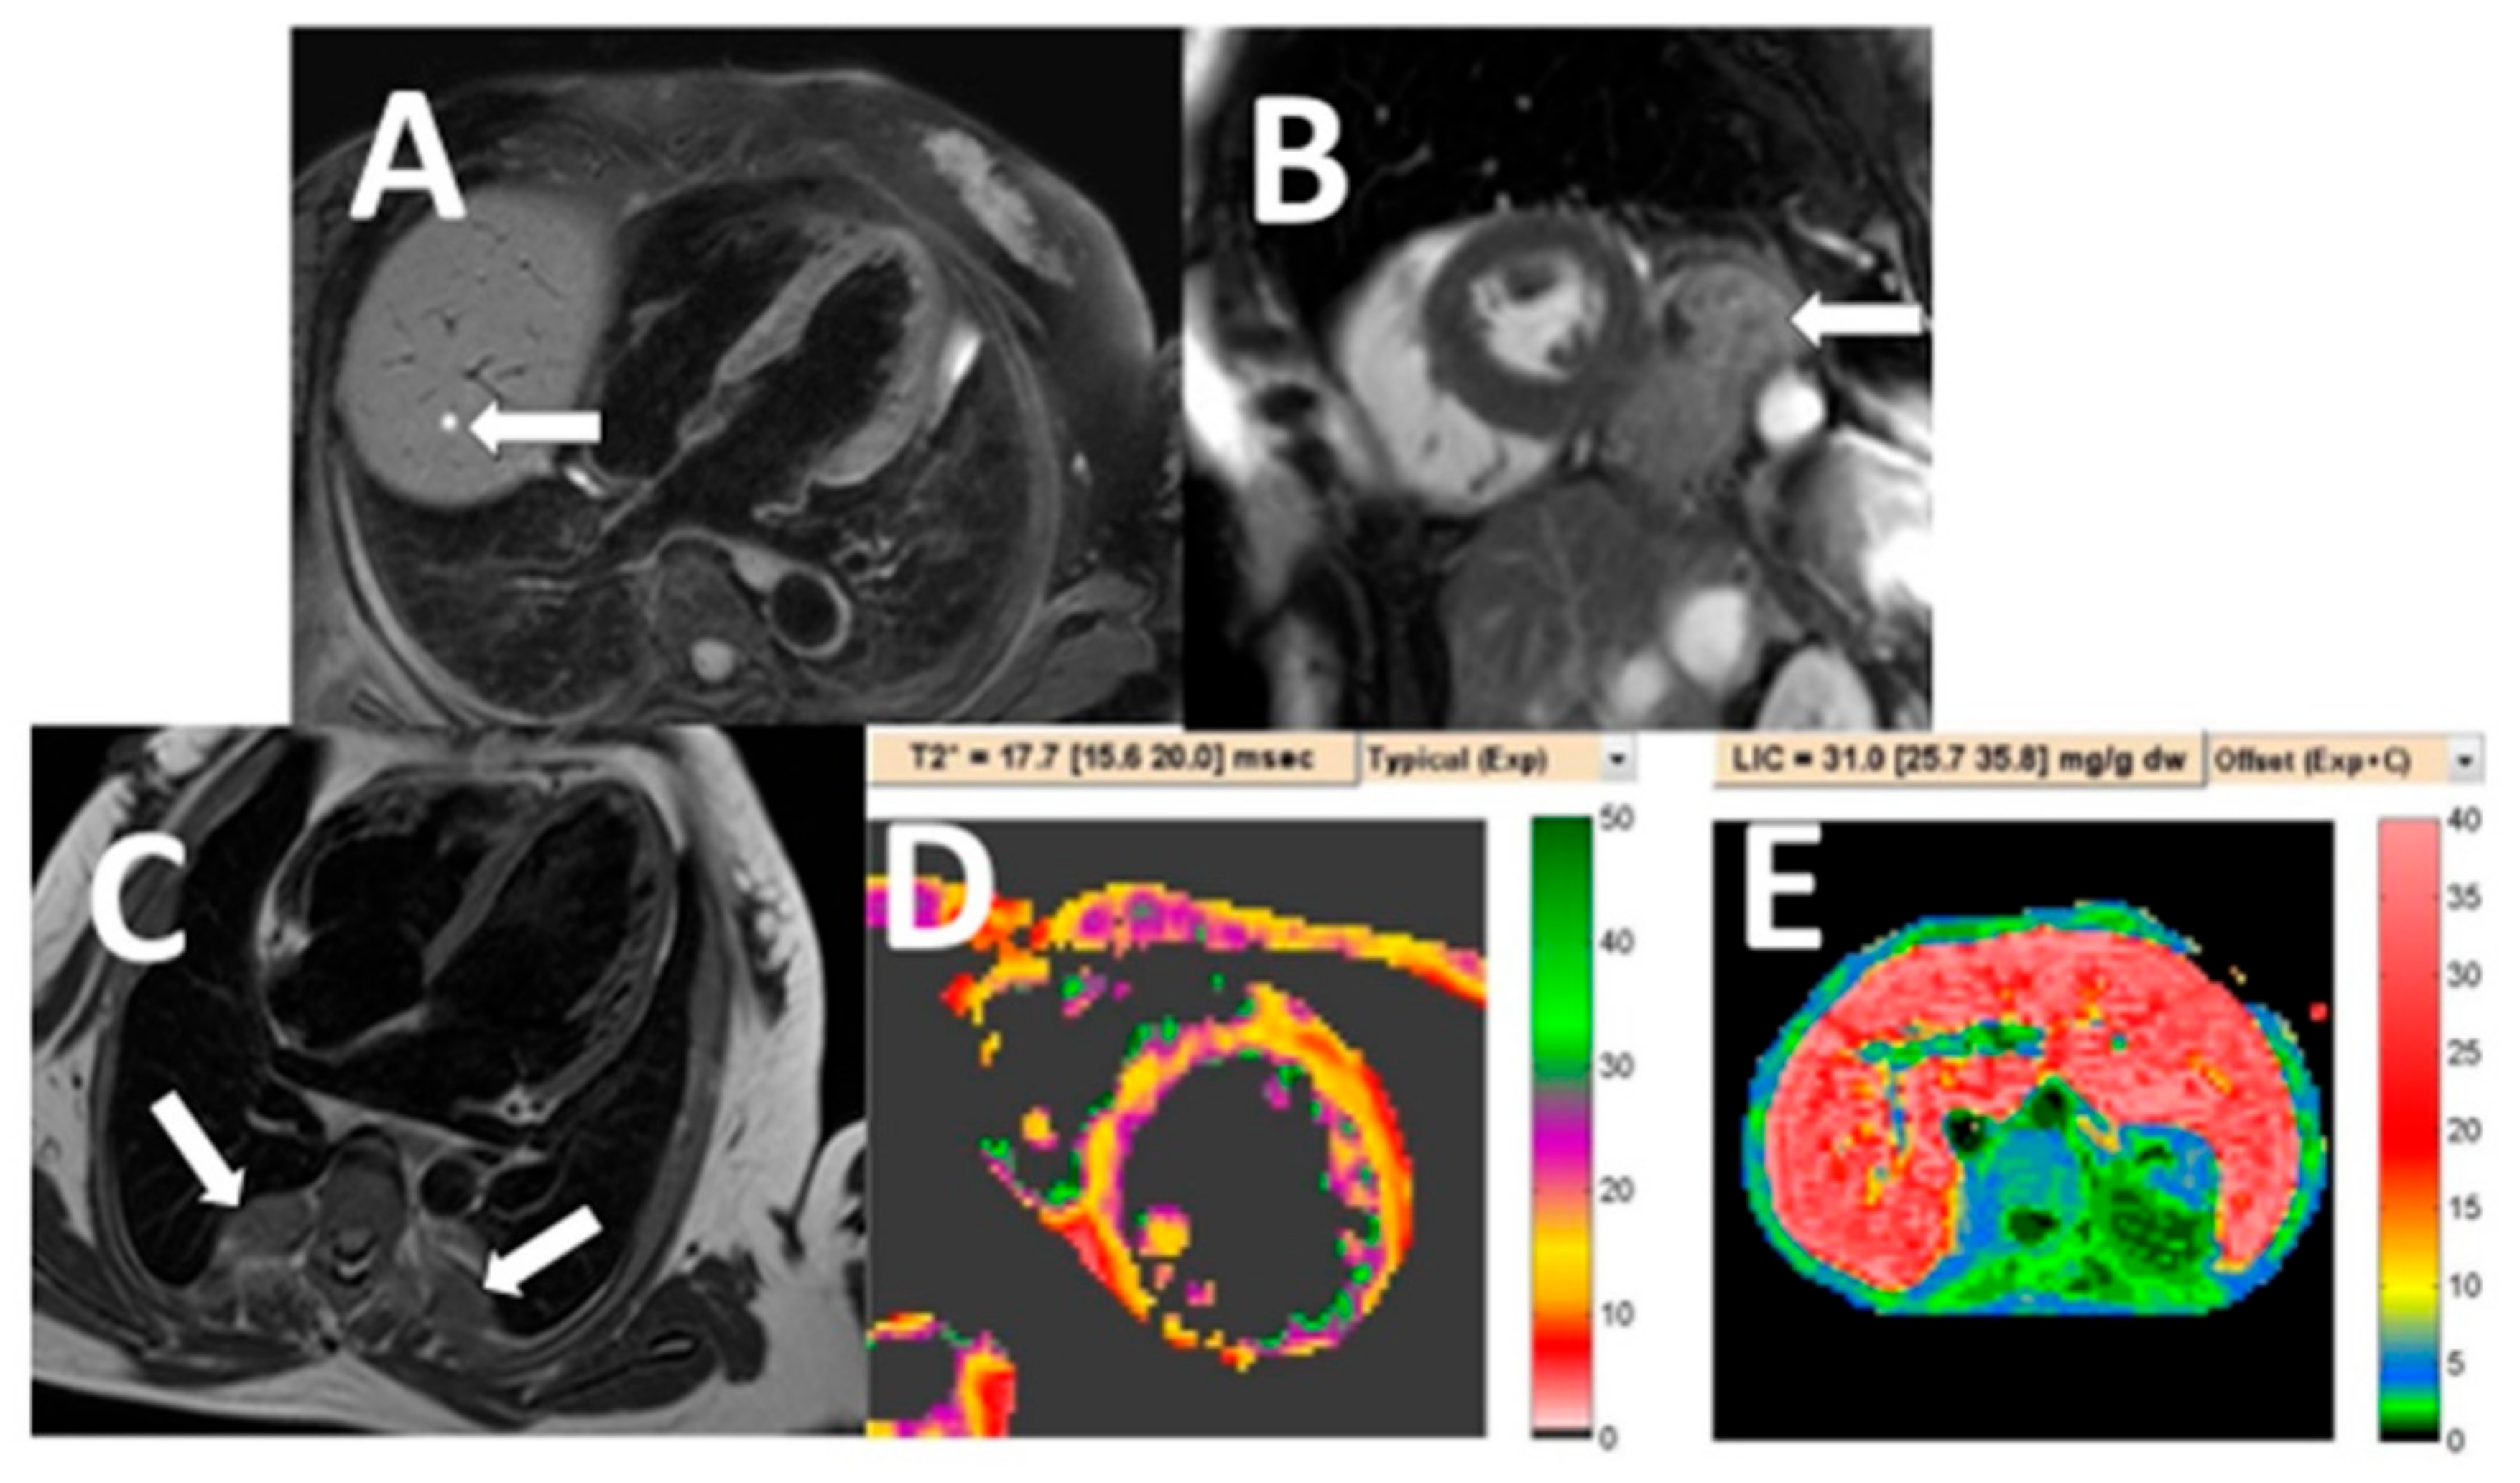

| Clinically significant NCA (n = 25) | |

| Malignancy | 18 (72) |

| Cholangiocarcinoma | 7 (28) |

| Lung cancer | 4 (16) |

| Hepatocellular carcinoma | 3 (12) |

| Breast cancer | 1 (4) |

| Renal cell carcinoma | 2 (8) |

| Bone metastasis | 1 (4) |

| Pulmonary thromboembolism | 2 (8) |

| Aortic dissection | 2 (8) |

| Aortic aneurysm | 3 (12) |

| Extramedullary hematopoiesis | 5 (5.4) |